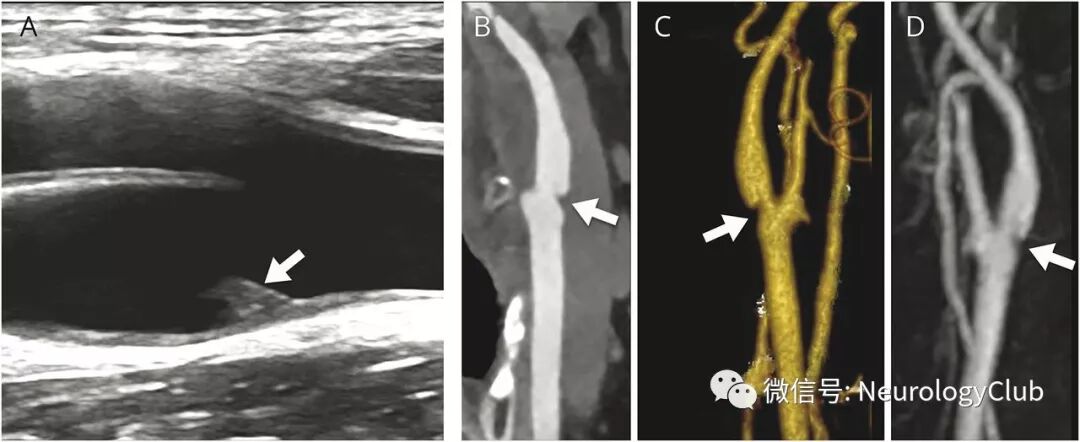

(图1:多普勒超声[A],CT血管造影[B-C]和3D增强MR血管造影[D]可见颈动脉蹼;引自:Renard D, Hampton J, Keita M, Freitag C.Teaching NeuroImages: Multimodality imaging of carotid web.Neurology. 2018 Apr 24;90(17):e1541.)